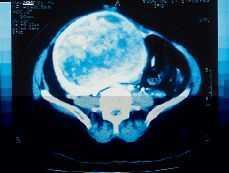

La historia clínica corresponde a una paciente de 57 años que acudió al médico por dolor abdominal inespecífico de unos días de evolución. Entre sus antecedentes, figuraban apendicectomía previa y diabetes mellitus. En el estudio ecográfico ginecológico, se observó una imagen de masa uterina grande, que excedía de los límites de la pantalla del monitor, sólida. Los anejos no eran apreciables, probablemente por el tamaño de la masa. La TAC informaba de un tumor sólido retrouterino, de unos 20 cm, que comprimía las estructuras retroperitoneales (Fig. 1). Dado el tamaño de la lesión, se decidió la exéresis. Se practicó histerectomía con doble anexectomía.

Figura 1. Tomografa computerizada que muestra el leiomioma uterino. Los ovarios no son visibles.